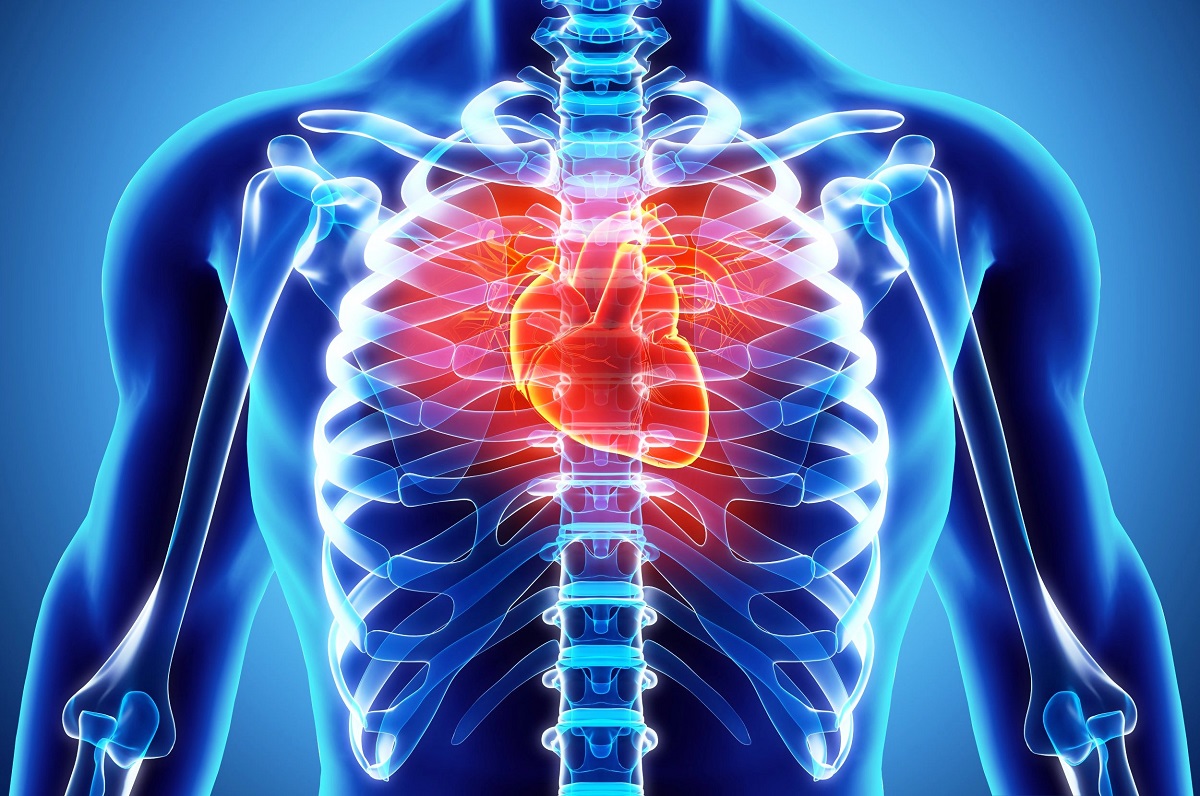

Предупредувачки знаци: Овие симптоми покажуваат дека е време да посетите кардиолог

Обрнете внимание на симптомите затоа што некои од нив не се безопасни како што изгледаат, па ако ги почувствувате, посетете кардиолог. Еве кои симптоми укажуваат на кардиоваскуларни заболувања и кои фактори го зголемуваат ризикот од нив.

Болка во градите

Болката во градите укажува дека нешто не е во ред и дека треба да направите контрола. Иако срцето не е единствената причина за оваа болка, најдобро е да посетите лекар и да се ослободите од сомнежите.

Болката која е поврзана со срцевите заболувања има и придружни симптоми како што се чувството на тежина и притисок во градите, болка која се проширува на грбот, на вилицата, на рамењата и на рацете. Оваа болка обично трае неколку минути и се повторува неколку пати во краток временски период. Болката е проследена и со кратко дишење, со потење, со вртоглавица и со гадење.